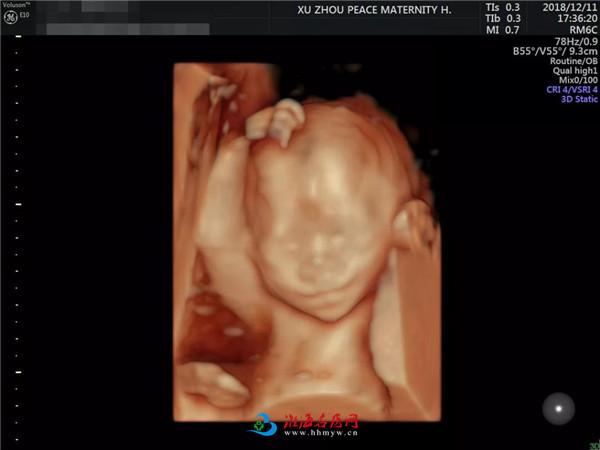

娴熟运用美国E10彩超设备

超高清的四维成像▼